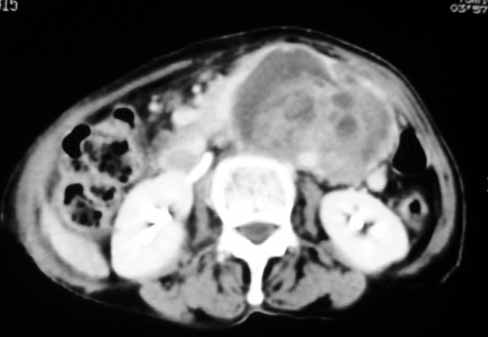

以下是引用天南地北在2007-4-30 17:42:00的发言:[br]增强扫描显示腹主动脉给包绕、推移。肿块不规则强化,[br]修正我在平扫的诊断[br]支持考虑:间叶源性肿瘤可能性大

以下是引用余辉在2007-4-30 18:01:00的发言:[br]病灶前方的条状增强影是什么?若是胰腺,位置似乎有点低,若是十二指肠,似乎又不诫该是那样强化,姑且将其看作胰腺吧,那么考虑来源于胰腺粘液囊腺瘤可能性大,其次考虑来源于肠系膜或者后腹膜的肿瘤如平滑肌肉瘤,异位嗜铬细胞瘤及淋巴瘤等。

以下是引用zyx168在2007-4-30 23:24:00的发言:[br]考虑:间叶源性肿瘤可能性大